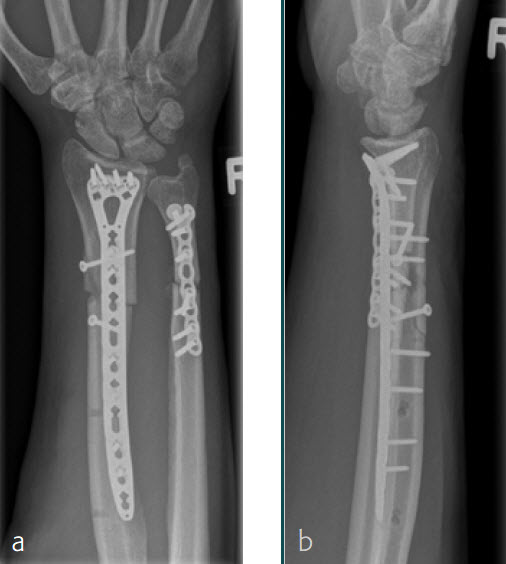

Fig 1a-b Preoperative x-rays.

Fig 3ac Immediate postoperative x-rays.

Fig 4ab X-rays 3 months postoperatively.